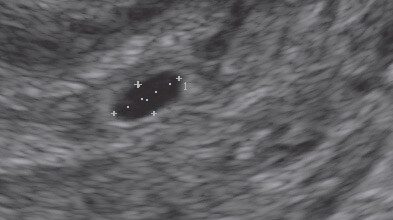

3/25

La evolución del feto a través de ecografías

Ecografía con 3 semanas: el saco gestacional mide 7 mm de diámetro.